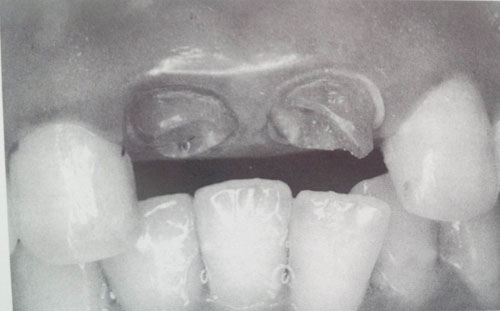

やむなく歯の神経の治療になった歯の頭は

残念ですが、このように

バッサリと削り落として歯の根っこだけの状態にしてから

治療を行なうこととなってしまいます。